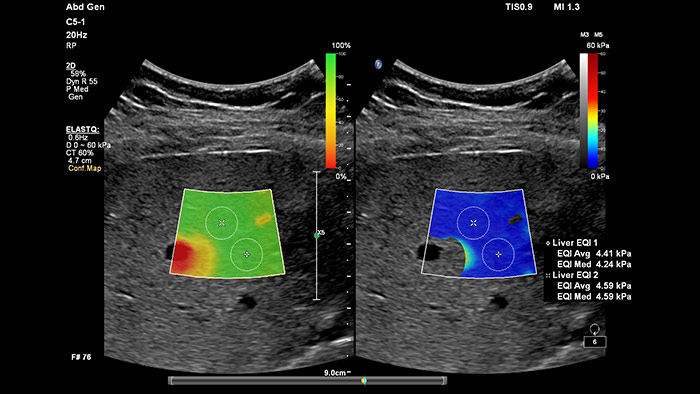

Elastografía por onda transversal de imágenes con ElastQ

La elastografía por ultrasonidos de onda transversal ofrece un método no invasivo, reproducible y fácil de poner en práctica para evaluar la rigidez tisular. Los estudios realizados apuntan a que, en lugar de un costoso y doloroso procedimiento de biopsia, una sencilla exploración por ultrasonidos con elastografía de onda transversal podría convertirse en el procedimiento habitual para evaluar el estado de las enfermedades hepáticas.  La elastografía por onda transversal de alto rendimiento de las imágenes con ElastQ incluye la evaluación cuantitativa de la rigidez tisular, codificada con colores, en extensas regiones de interés (ROI) en tiempo real.  Las imágenes con ElastQ también ofrecen la posibilidad de efectuar mediciones retrospectivas en imágenes almacenadas; además, una exclusiva pantalla con un mapa de confianza emplea el análisis inteligente para ofrecer la garantía adicional de que las mediciones del usuario se han obtenido en zonas tisulares con una propagación adecuada de ondas transversales.

Evaluación hepática no invasiva simplificada

La medición de la rigidez hepática se obtiene en cuestión de segundos por medio de una sencilla exploración no invasiva.